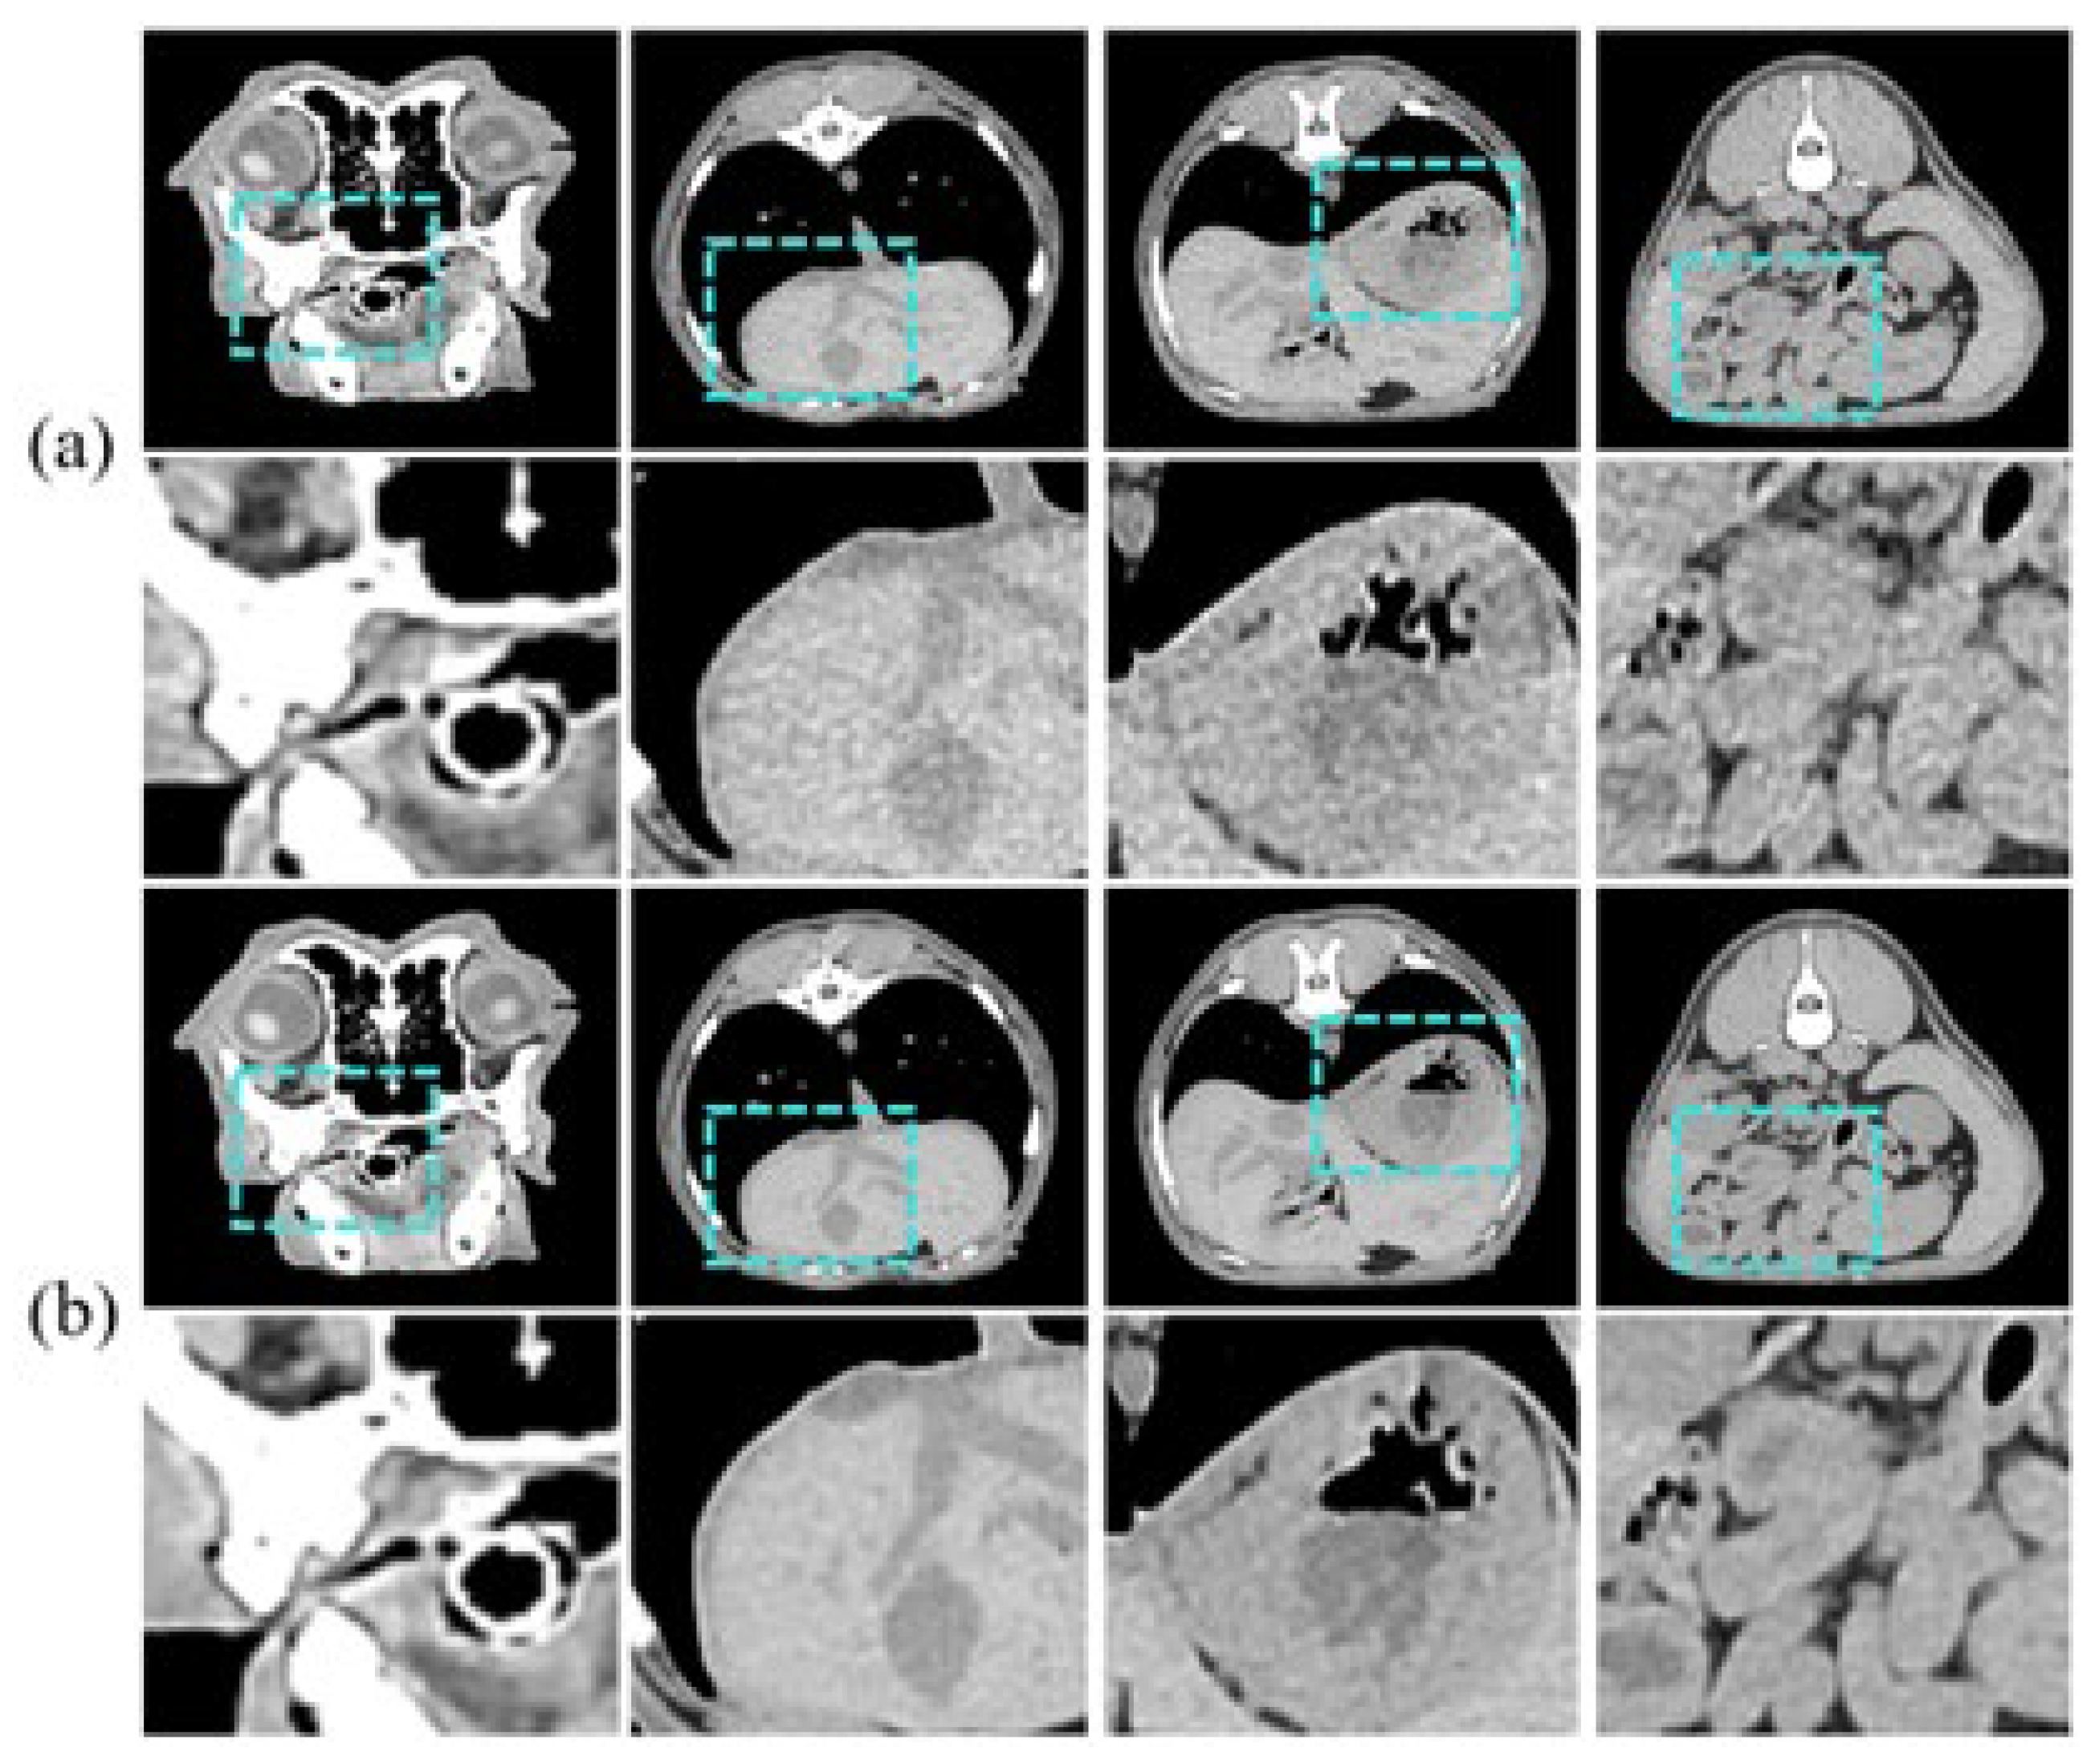

In this study, we used unmatched pairs of LDCT and SDCT images of 10 clinically healthy dogs provided by the Animal Hospital of Konkuk University. We observed ethical considerations, and Institutional Review Board (IRB) approval was obtained for the animal experimentation. The training data consists of 3458 axial slices of LDCT and SDCT images of 9 dogs, respectively, and the test dataset consists of 941 axial slices of one dog. Figure 5 is an example of an input sample. The CT images are grayscale and have a pixel size of 512 × 512. Coronal currents were acquired using 30 mA and 150 mA for LDCT and SDCT, respectively.

For the purpose of comparing noise reduction performance, we employed three distinct deep learning models. RED-CNN [40], rooted in residual learning, enhances resolution by extracting features from high-resolution images at each layer and adding these features to the output of the previous layer. We utilized HFS to compare its effectiveness in feature extraction from images. WGAN-VGG [3] is a model based on the Wasserstein GAN (WGAN) [41], which improves the stability of GANs and the quality of generated images. We used it to compare with the anti-aliasing and stability effects of BlurPool and the regularization term that we used. Lastly, DU-GAN utilizes a gradient domain discriminator to enhance edge information and reduce streak artifacts caused by photon starvation. It focuses on increasing edge sharpness and reducing streak artifacts to generate high-resolution images. Therefore, we chose this model for comparison with the multi-scale discriminator.

Figure 7 shows the resulting images of the proposed model and the comparison models. Figure 7b is the result image for RED-CNN, indicating significant noise reduction compared to the LDCT images, though sharpness is still lacking. Figure 7c shows the result for WGAN-VGG, which is sharper, but shows less noise reduction. Figure 7d shows the results for DU-GAN, where the edges are cleaner and the denoising is effective, but sharpness is still an issue. Figure 7e shows our proposed model, which addresses the shortcomings of the previous models and best represents the features of SDCT.

Our results demonstrate that our proposed model outperforms comparative methods in both perceptual and quantitative evaluations. In our study, the results show that our model outperforms the comparative methods in both perceptual and quantitative evaluations in Figure 7 and Table 2. In addition, in Figure 6 and Table 1, the effectiveness of the proposed scSE method for denoising LDCT images in animal imaging was demonstrated. Through three ablation studies, we compared the performance of cSE alone, sSE alone, and the combined scSE method, revealing distinct advantages and limitations associated with each approach. The successful implementation of the scSE method underscores the importance of innovative approaches in addressing the challenges associated with LDCT imaging in veterinary medicine.

Figure 5. Image samples for training, showing diverse regions/tissues: (a) is LDCT and (b) is SDCT.

Figure 7. Results of the proposed model and other models: (a) LDCT, (b) RED-CNN, (c) WGAN-VGG, (d) DU-GAN, (e) Ours, and (f) SDCT.